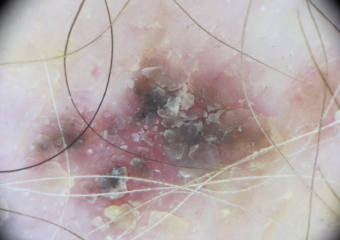

Actinic keratosis on head or neck. Photo: International Skin Imaging Collaboration at isic-archive.com